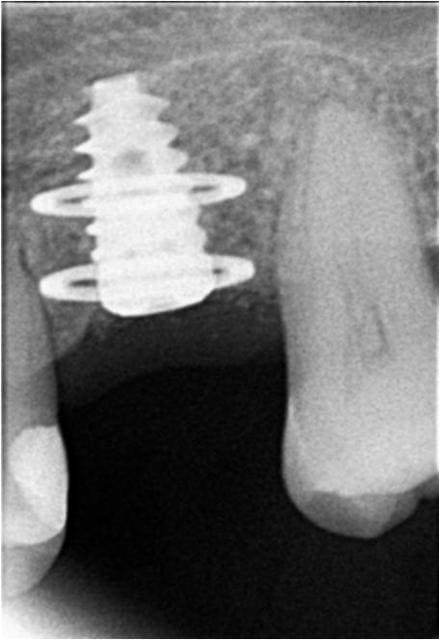

salut pp

je ne me rappelle plus la référence de l'implant disk en voilà une radio et ce que j'ai fait pour rattraper le coup

05/01/2011 à 00h12

voici les radios

Diskimplants q4ij2p - Eugenol

Diskimplants3 xdjbqv - Eugenol

Super

Voici donc un cylindre à double disk ;-)

Et puis chapeau de ne pas avoir déposer tes disks comme bcp le préconise car ils étaient intégrés et il n y vaiat aucune raison de faire autrement que ce que tu as fait

05/01/2011 à 00h27

En y regardant de plus près , tes radios montrent un soutien osseux assez limité au niveau des dents voisines

Si elles sont mêmes légèrement mobiles , stt si elles pompent un peu verticalement, il est possible que ton implant soit devenu avec le tps la seule vraie butée occlusale ds le coin d où sa casse ...

Peux tu me dire si des dents bougent ds le voisinage ???